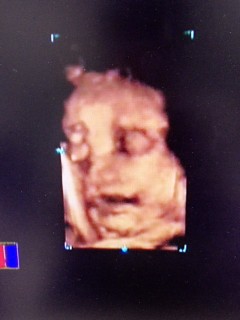

写真:39w1d:みみちゃんさん:2600g

大きなぽちゃぽちゃベイビーで、先生何度も手をどかそうとしてくれるけど完全に目を隠してる!

エコーでは最近口を開けている事が多いです。